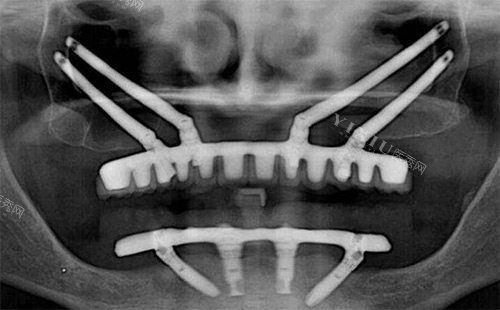

传统种植牙要求牙槽骨至少有8-10mm高度,但上颌骨重度萎缩患者(牙槽骨高度<5mm)根本达不到标准。穿颧种植直接绕过萎缩的牙槽骨,把3-5cm长的种植体植入颧骨(眼眶外下方骨质厚达15-20mm),相当于在“贫瘠土地”上找到了“肥沃新土壤”。

传统植骨需等待3-6个月愈合,穿颧种植无需植骨,全口无牙患者植入4-6颗穿颧骨植体后,当天就能改善基本咀嚼功能。临床数据显示,其5年成功概率达95.7%,与常规种植牙(97%)相近。

穿颧种植需穿透颧骨和翼突骨,这两个区域密布三叉神经分支、面神经和血管。若操作偏差1.5mm,就可能导致神经损伤,表现为面部麻木、肌肉运动障碍或持续性疼痛。经验不足的医生操作神经损伤率高达8%,而资历深医生可控制在1%以下。

骨裂:若患者骨密度低或操作力度不当,可能引发颧骨骨折或颌骨分裂。

种植体异常:种植体过长可能穿透颧骨表面形成突起,影响面部美观;骨结合失败则导致松动脱落。